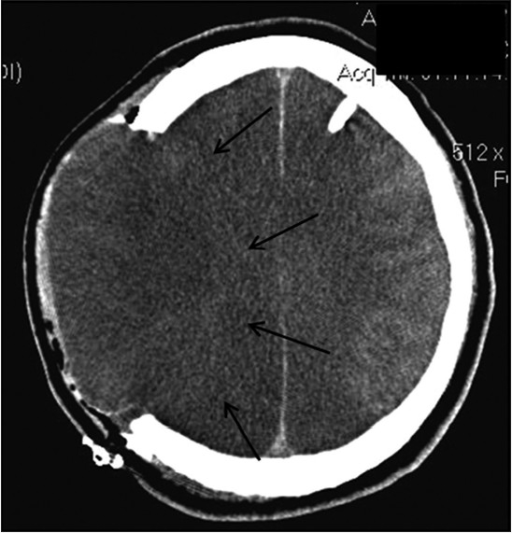

Swelling in his left parietal area and a tenderness on his left wrist. This is because, the computer tomography (ct) scans finding on each stage varies among hypodensity area detected by ct previously may gradually expand, involving both gray and white as time progresses, in the subacute phase, brain swelling and mass effect will gradually build up within. A ct scan can help diagnose many types of cancer.

Computed tomography (also cat or ct scan) of the brain (cerebral hemispheres, cerebellum and brain stem.) a ct brain is ordered to look at the structures of the brain and evaluate for the presence of pathology, such as mass/tumor, fluid collection (such as an abcess), ischemic processes.

It will scan across the entire image and would create a coloured mask to highlight exact locations affected with a certain level of confidence. Abdulwahab, rizgary teaching hospital, erbil. This is because, the computer tomography (ct) scans finding on each stage varies among hypodensity area detected by ct previously may gradually expand, involving both gray and white as time progresses, in the subacute phase, brain swelling and mass effect will gradually build up within. The cat scan can also show bleeding, swelling, bone and tissue calcification that would be caused by a cancer.